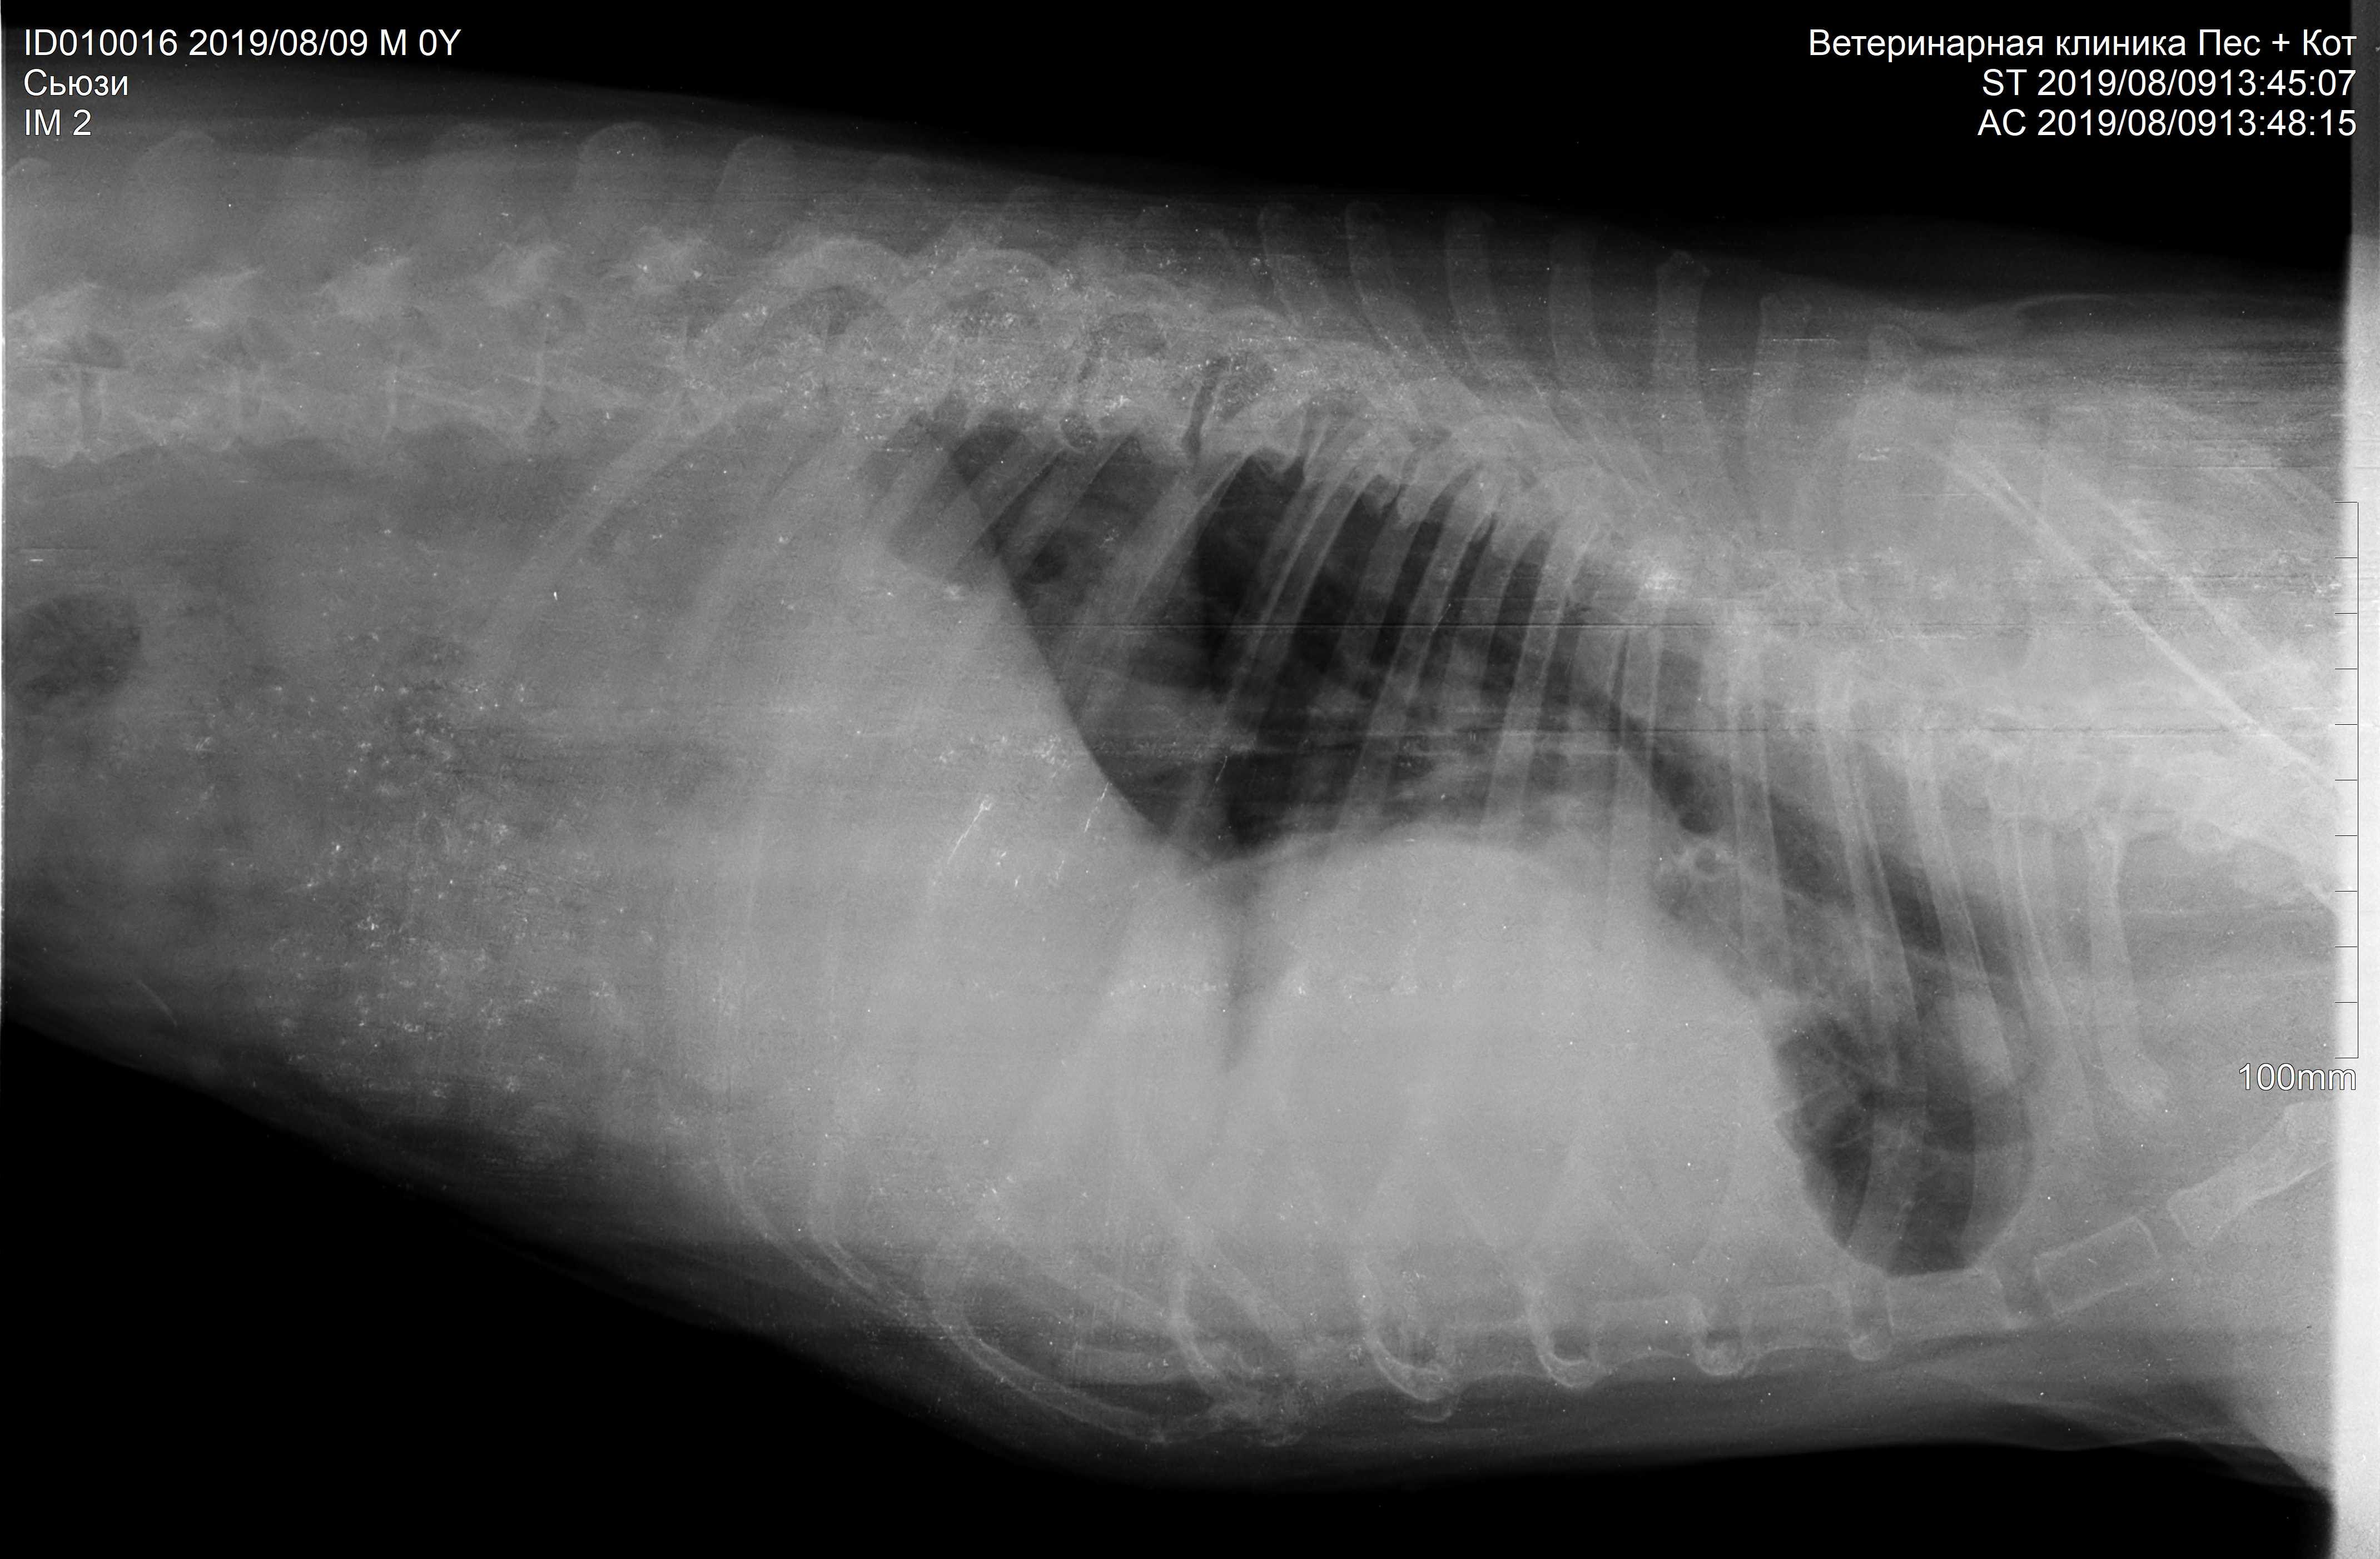

Pet's info: Dog | Boxer | Female | spayed | 10 years and 9 months old | 35 lbs

What's on the Х-ray? Please help me understand. 10-year boxer dog, severe non-productive cough, loosing weight, weakening. Good appetite, good looking hair.

Hello. Unfortunately it looks like Suzy has a tumor or some other very large space occupying mass involving almost 75% of her thoracic cavity. Suzy would need further diagnostics, such as a biopsy, to identify exactly what is in her lungs, but the condition looks very advanced. I hope your veterinarian is making her as comfortable as possible. Thanks for using Petco Pet Education Center, formerly Petcoach.